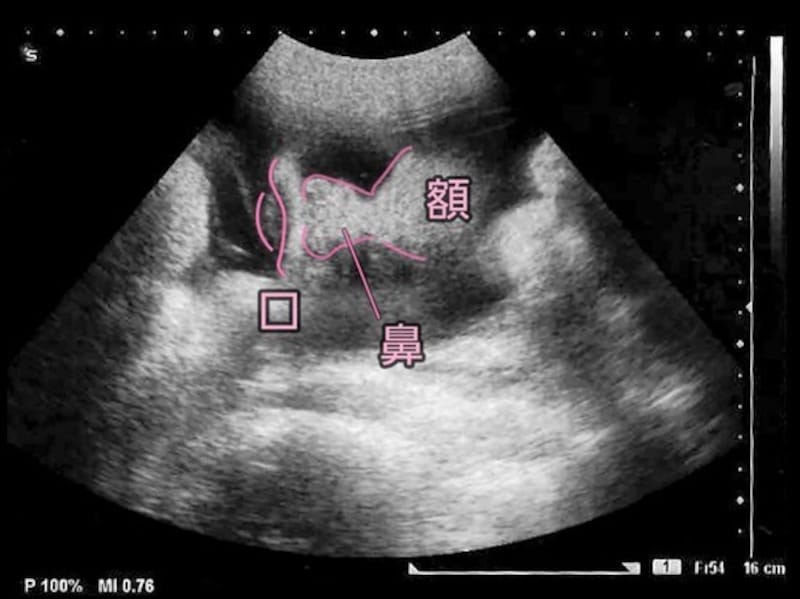

妊娠37週目の胎児の発達

- 妊娠37週目:受精から245~251日目

- 胎児の大きさ:頭殿長(座高)が48~49cm

- 胎児の体重:2200~3100gほど

- 母体の変化:正期産の時期に。前駆陣痛を感じることも

赤ちゃんは背を丸めたスタイルをとっています。手足を動かすスペースはあまりないもののモゾモゾと動いていますが、大きな動きがないだけに、お母さんには胎動が少なくなったと感じられるかもしれません。